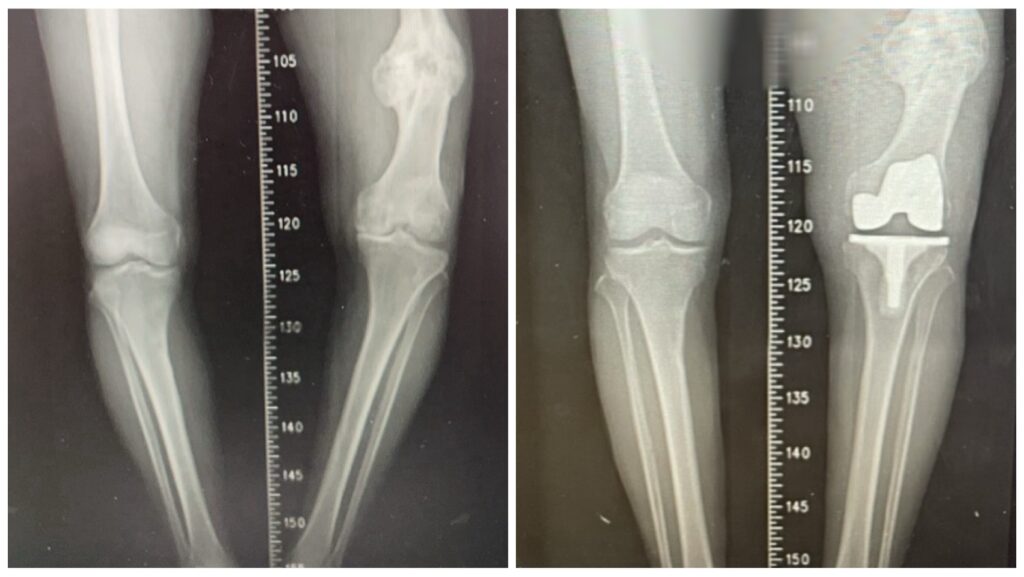

左為術前,右為術後。(記者孫義方攝)

〔記者孫義方台中報導〕台中豐原八十七歲的黃翁,數十長年來深受長短腳與膝蓋疼痛所苦,因他年輕時左側股骨骨折,當時治療不佳導致骨癒合不良並出現內翻變形,最初兩下肢僅有約兩公分長度差距,隨著時間推移逐漸惡化,最後擴大至近七公分,讓他不僅步態不穩,更引發腰部與下肢不適,經衛福部豐原醫院骨科江福財醫師評估,決定進行人工膝關節置換手術,最終成功改善症狀,讓黃翁穩健走下去。

江福財醫師說明,這次手術的困難在於同時面對「陳舊性股骨骨折造成的骨骼變形」與「長達七公分的下肢長度差距」,因此手術除了進行人工關節置換,還需進行精準的韌帶平衡。輔以電腦導航與影像輔助技術,得以在修正骨骼角度的同時兼顧關節周圍韌帶平衡,避免造成膝關節不穩定,行動困難。

這次手術沒採用截骨矯正方式,而是單靠人工膝關節置換,直接解決患者最在意的長短腳問題,最終成功將雙腿長度差縮小至約二點五公分,大幅改善步態,術後患者無需輔具即可下床行走,術後必須持續進行肌力訓練與步態矯正,以確保關節穩定性,並定期回診追蹤,以獲得最佳治療成效,逐步恢復生活自理能力。